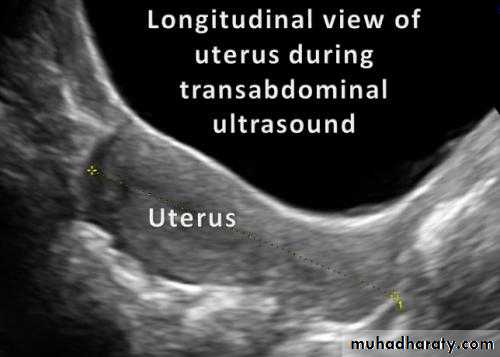

Normal Uterus in longitudinal viewUterine Pathology